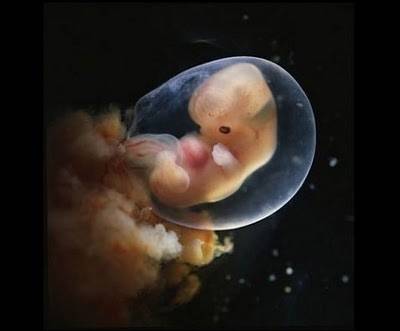

5 седмици стар ембрион – лицето почнува да се оформува…

7 седмици стар ембрион…

8 седмици стар ембрион…